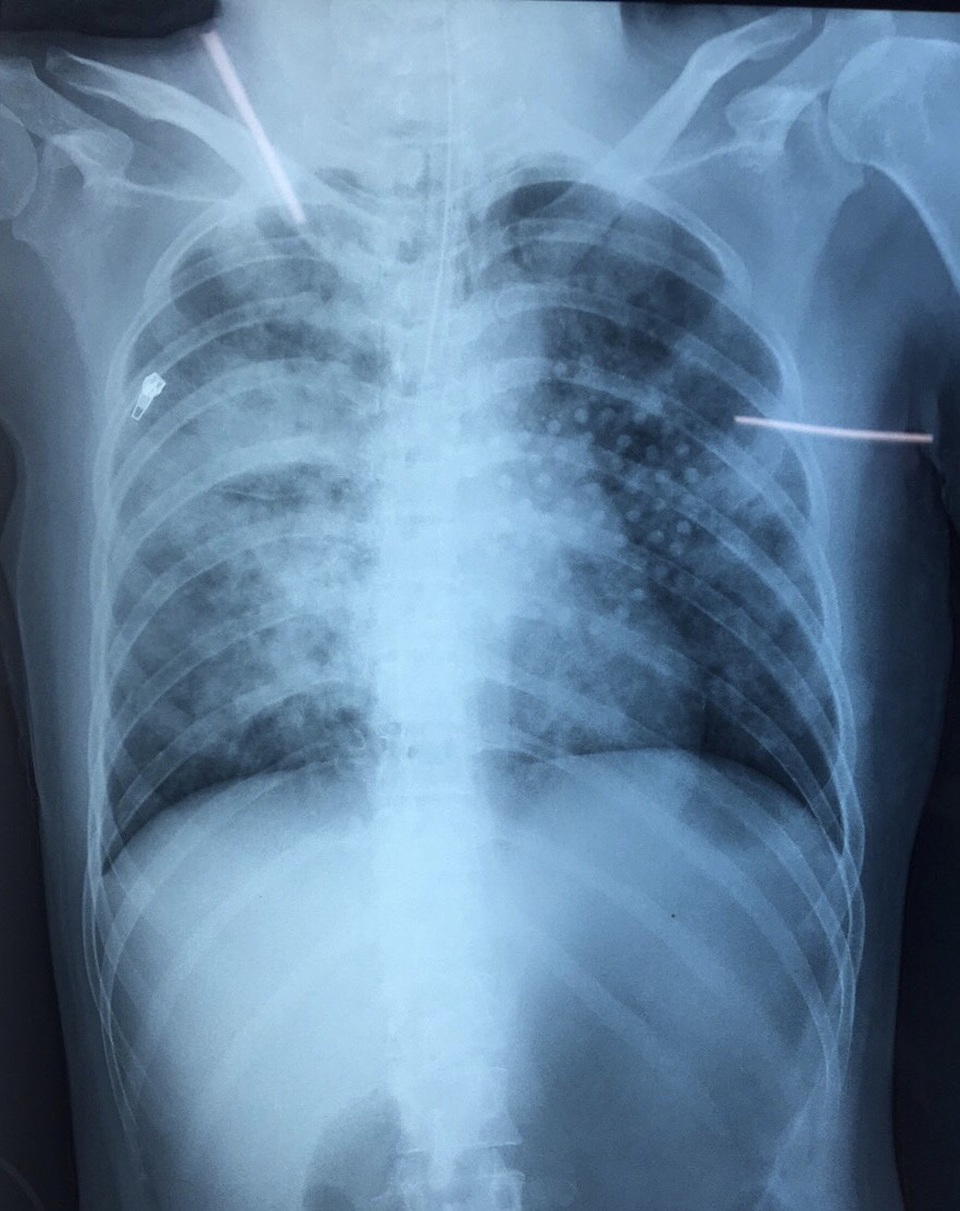

Hình ảnh X-quang cho thấy, bệnh nhân bị tổn thương 2 bên phổi lan tỏa

Tại bệnh viện ĐKTƯ Cần Thơ, bệnh nhân có chỉ định thở máy, X.quang tim phổi thẳng phát hiện mờ lan tỏa 2 phổi, gãy xương sườn.